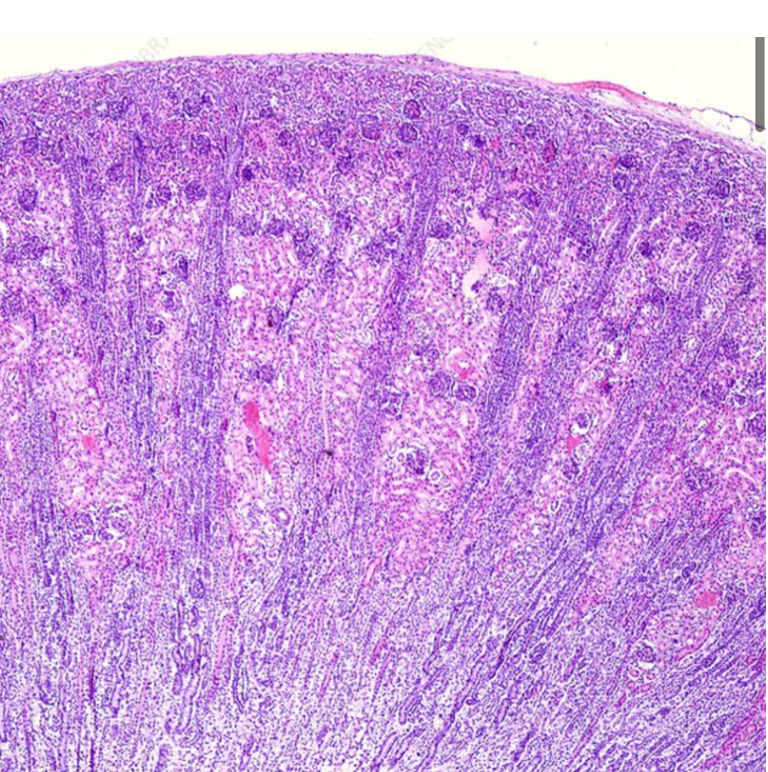

What organ is this showing

The kidney

Destuinguish the cortex vs the medulla of the kidney

Cortex is full of globules whereas, the medulla is more tubule